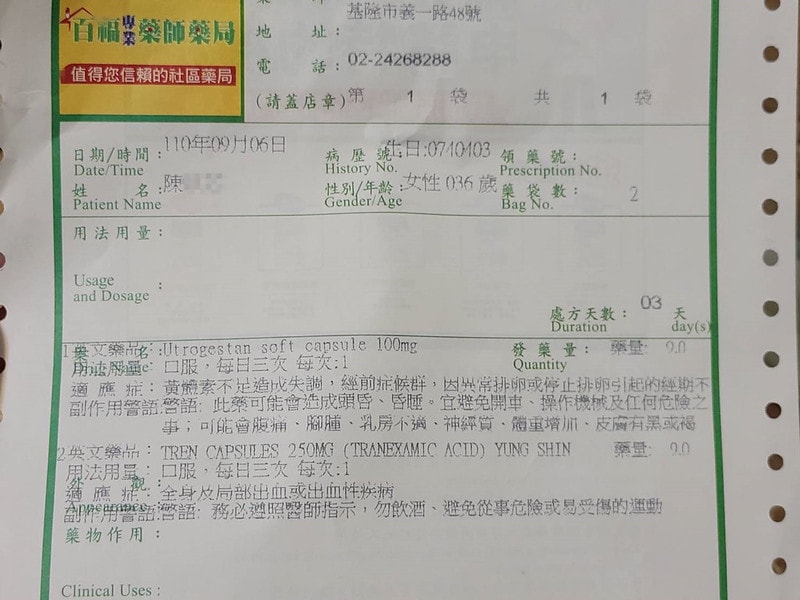

關於安胎藥

那時候拿到的藥長這樣

會開黃體素和安胎藥給你,就是乖乖吃